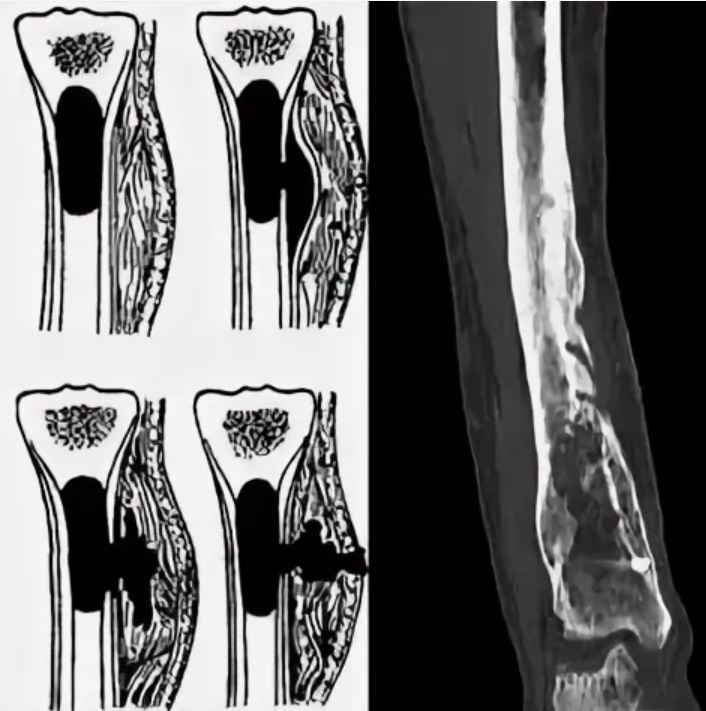

Остеомиелит Лечение Фото